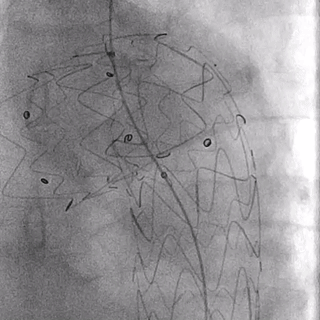

03. 控制性降压至90/55mmHg左右,沿右股动脉入路引入超硬导丝及华脉泰科胸主支架PTBS3430180,术中沿LCCA后缘处缓慢释放1-2节,再次造影确认定位精准后继续释放主体支架,造影示覆膜支架未覆盖LCCA,覆盖LSA。

04. 沿左肱动脉引入5F Ver导管,头端垂直抵住主体支架覆膜,引入0.035″长泥鳅导丝配合导管顺利破膜,进入主动脉。

05. 0.035″长泥鳅导丝进一步超选进入降主动脉段,并沿右股动脉引入抓捕器抓取泥鳅导丝建立导丝路径,依次逐级使用4*40mm、6*40mm、8*40mm Amanda球囊扩张破膜处。期间可见明显受压切迹影。

06. 沿右股动脉引入8F长鞘,置入8*50mm Viabahn覆膜支架于开窗处,远端避开左椎动脉,近端超过覆膜支架1cm并完成释放。

07. 最后行全主动脉造影示LSA开窗支架重建良好,近端主体支架定位显影良好,腹主动脉右肾动脉、腹腔干动脉及肠系膜上动脉显影较支架植入前明显改善。